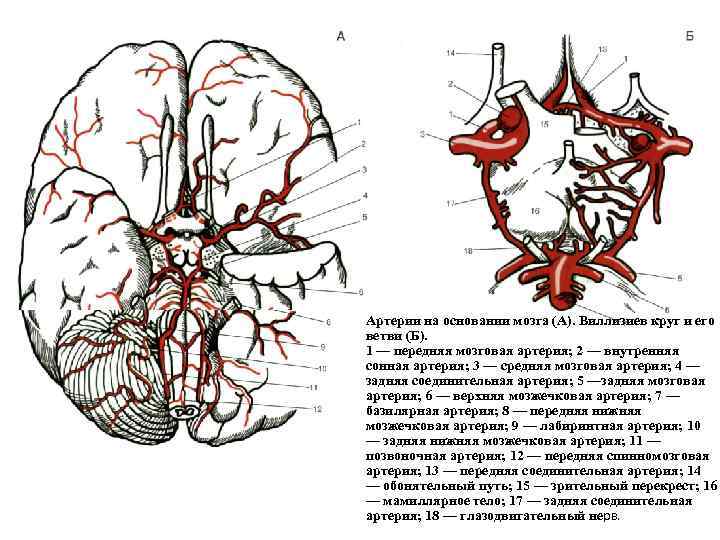

Анатомия: Задняя соединительная артерия мозга

:max_bytes(150000):strip_icc()/CircleofWillis-87378170-3ece0502a02949dd82310d723e0d4c98.jpg)